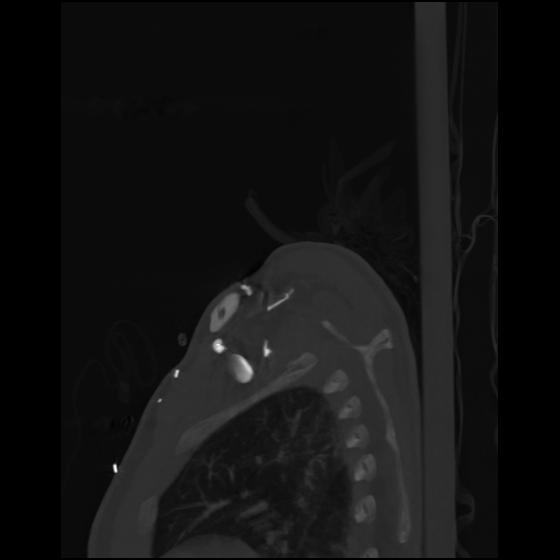

24 ANGIO,CE,Sag-MIP,5.000,ANGIO,Sag-MIP,